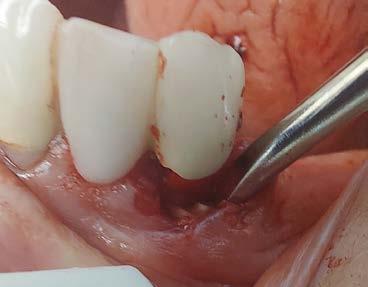

Technique for extracting tooth or root tip from underneath fixed partial denture emphasizes use of magnification from dental loupes or dental surgical operating microscope for precision when performing technique-sensitive procedure. Case report.